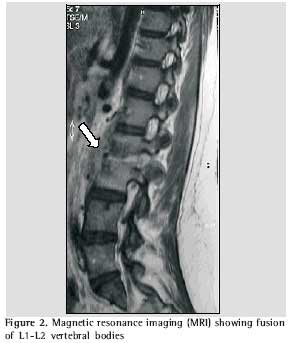

As her condition worsened, leading to difficulty in moving about, she was advised to seek medical assistance at a neurosurgery outpatient clinic, where she was submitted to lumbosacral spine computed tomography, magnetic resonance imaging, chest X-ray, biopsy of the affected site and blood count (including determination of erythrocyte sedimentation rate). Computed tomography revealed irregularity and reduction of the articular space between L2 and L3, concomitant with sclerosis of the corresponding vertebral bodies, as well as fracture in L2. The vertebral disk between L5 and S1 presented a slight protrusion, without causing significant intrarachidian repercussions. The findings suggested the possibility of an inflammatory or infectious process, or both, involving the L2 and L3 vertebral bodies, as well as the corresponding intersomatic disk (Figure 1). Magnetic resonance revealed reduction of the L2/L3 disk space and cold abscess in the corresponding area, which reinforced the possibility of a spondylodiscitis-like process (Figures 2 and 3).